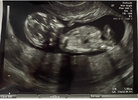

Maluch ma wszystko na miejscu, serduszko bije 155ud/min.

Ryzyka trisomii powyżej 1:16000

Ryzyko przedwczesnego porodu dość duże, bo 1:154, ale doktor powiedział, że takie ryzyka się często zdarzają i żeby się nie przejmować 🤞🏻

Termin porodu wyszedł mi teraz na 2 grudnia, zamiast 6 grudnia.

Ja miałam już wyniki testów z krwi i to są zestawienia z wynikami :)

Załączniki

• IMG_9725.jpg